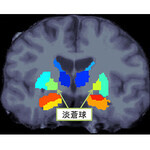

阪大など、統合失調症患者の脳で左右の体積がアンバランスな部位を発見